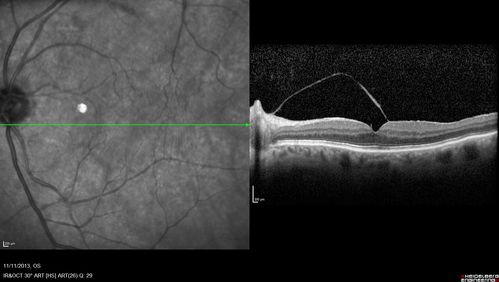

Vitreomacular Traction -> Macular Hole -> Aborted Macular hole

Progression of VMT in both eyes over time